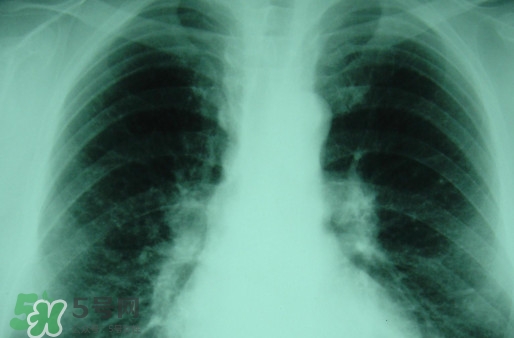

塵肺病多半是因?yàn)榉尾课牖覊m導(dǎo)致呼吸不順暢,引發(fā)細(xì)菌感染的病癥,而且隨著近年來塵肺病人得增多及死亡率,國家對此發(fā)布了相關(guān)政策。那么,塵肺病吃什么藥能清肺?塵肺病國家有什么政策?

很多人不知道,其實(shí)塵肺病分為無機(jī)塵肺和有機(jī)塵肺兩種?;颊哂捎谠谌粘5墓ぷ髦兄虚L期吸入生產(chǎn)性粉塵(灰塵),這些粉塵在肺內(nèi)滯留,從而引起的了塵肺病這種全身性疾病,很多人對此認(rèn)識并不清楚。